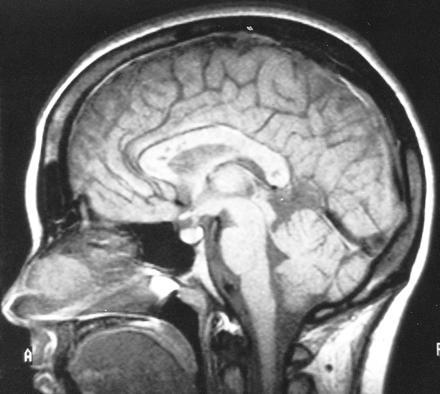

多病灶的幕上的白质病变,包括胼胝体(图1),在所有27个病人,有频繁的参与小脑,中间小脑总花梗,和脑干图1,表)。病变众多,往往是小(3 - 7毫米)但有些小病变成为支流和一些大的(> 7毫米)。19病人实质增强,当明显,导致大脑的粟粒状的外观(图2)。胼胝体的损伤通常是小的,并且涉及中央与周边的相对保留纤维;增强是变量。急性胼胝体的病变(图3)中观察到的活动脑病取而代之的是一个“充满”/穿孔先生出现在后续所有27例(图4),可能代表microinfarctions,没有出现在其他地方。胼胝体,最好在薄片(3毫米厚)矢状T1或T2矢状/质子密度加权图像,由一系列小(3毫米)中央孔相隔7毫米矢状T1和T2矢状/质子密度图像。这些扩展在整个长度的胼胝体。当急性(“雪球”)(见大图3)胼胝体的病变,慢性残余孔较大,尤其是在压部。线性缺陷有时看到的,可能反映microinfarction间接辐射在胼胝体轴突。中央孔(见图4)被认为是由于横向辐射的胼胝体轴突的微型心肌梗塞的可能性。

有深的灰色基底节和丘脑病变19病人(参见表),通常体现在T2信号强度增加,质子密度,和天赋的图像。大病变类似“巨大陷窝”43并建议纹状体外动脉增的广泛参与。三个这样的病人显示这些病变显著增强,伴随着leptomeningeal增强。实质增强(见图2)有关的大脑区域,偶尔与leptomeningeal增强(见相关表)。串行扫描被执行,增强可能是更常见。脑病减弱和病人开始恢复,只有残余病灶中央(见胼胝体的洞图4)和一些白质病变。在两个病人,增加信号强度变化在胼胝体伴随着中央胼胝体的洞在最初的MRI检查。更严重影响病人、脑和小脑萎缩随之而来。在两个这样的实例,胼胝体越来越萎缩,前面提到的胼胝体的洞几乎消失了。

1991年,我们中的一个(A.D.G.)图像与中央黑洞先生发表在被错误地归因于ADEM的胼胝体。44病人的诊断是不清晰的,回想起来,几乎肯定是党卫军。中央胼胝体的孔女士在党卫军ADEM的不是一个特性或与学生相比,胼胝体的参与女士和亚当在底面的胼胝体隔接口。44尽管胼胝体的任何部分在党卫军可能受到影响,胼胝体的病变通常涉及中央纤维,与外围的相对节约。基于微血管血液供应(图5),44-46⇓⇓microinfarction应该涉及中央的胼胝体纤维。深灰色女士很少参与,但通常发生在儿童外,特别是在丘脑。47Leptomeningeal增强,指出在9我们的27例,与女士或ADEM不发生。